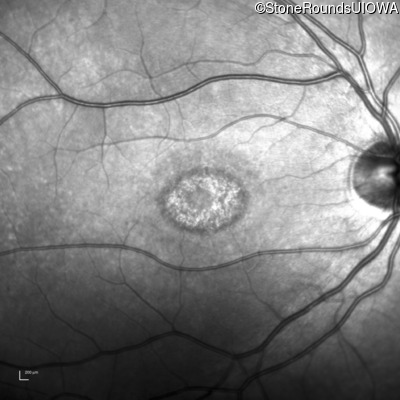

Infrared Fundus Photograph - Right - 20/50 -1

Exemplar